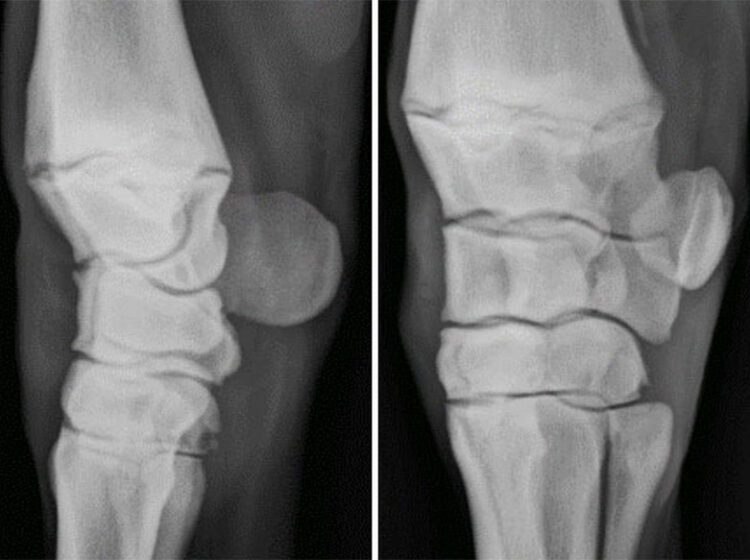

The early signs of osteoarthritis are important to recognise as changes to exercise/ training programs and pharmaceutical treatment can stop the formation or progression of this disease. These signs may include joint swelling, pain on joint flexion or subtle changes to the horse’s action, such as a wider limb stance, changing of lead legs, “hanging”, or a reluctance to work. If these signs are ignored more permanent changes can occur, resulting in radiographic changes of osteoarthritis and lameness. Chip fractures of the knee may occur as acute “overload” injuries but they more commonly occur in combination with osteoarthritis as this process causes a “weakening” of the bone. These chip fractures can occur as yearlings, although more commonly at 2 or 3 years of age. Although these chips can be removed, and many horses compete successfully, osteoarthritis cannot be reversed and ongoing modification to training programs and veterinary treatment are required to achieve racing success.